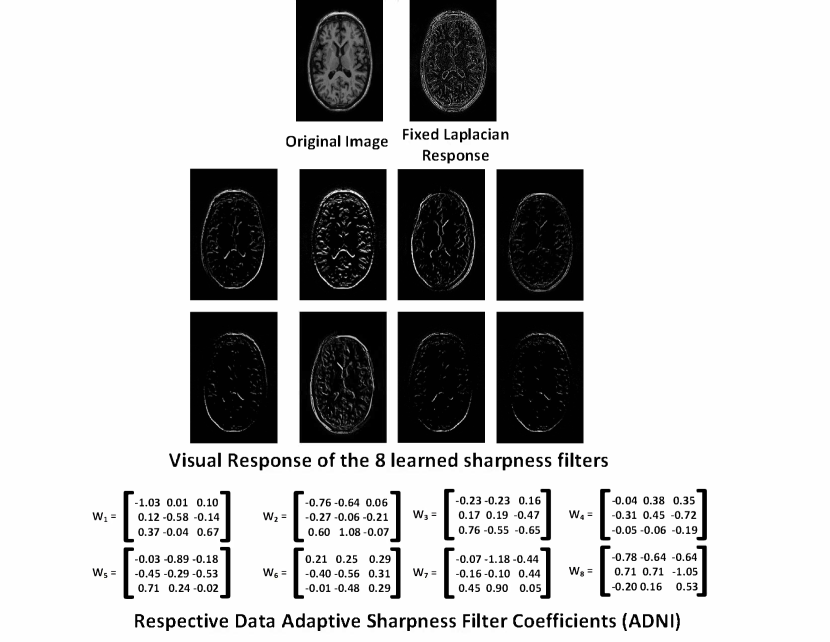

IV-B Significance of Priors: DNSP Variants

In this section, we report the results for different variants of the proposed DNSP to bring out the value added by each prior. We name the variants as follows: 1) DNSP-NP, network with no priors which is same as EDSR, 2) DNSP-LR, network with only low rank prior, 3) DNSP-FS, network with only sharpness prior with a fixed Laplacian layer, 4) DNSP-LS, network with only sharpness prior but with learnable sharpness filters and finally 5) DNSP-AP, network with both the priors included along with learnable sharpness filters. Table I shows the PSNR and SSIM on both the datasets. We can observe that priors improve the performance of the network. Among the individual priors, we observe the best performance for DNSP-LS, which is expected as the sharpness is enhanced via a data adaptive procedure that exploits available training. Figure 8 shows a comparison of the response from fixed laplacian filter and N=8subscript𝑁8N_{\mathcal{L}}=8 filters that are learned via DNSP-LS method. We can observe that spurious (undesirable/noise-like) edges that are present in the fixed Laplacian response are minimally seen in the response of the 8 filters learned based on data, which on the other hand lead to sharper images overall. It can be observed that the responses of learned sharpness filter depart from that of the Laplacian ( for example in exhibiting some directional orientation), which is a result of training image data adaptation.

Refer to caption

Figure 8: Response of the 8 learned sharpness filters (along with the corresponding filter coefficients) vs. the Laplacian filter on a sample image from the ADNI dataset, as well as the coefficients of the learned filters.